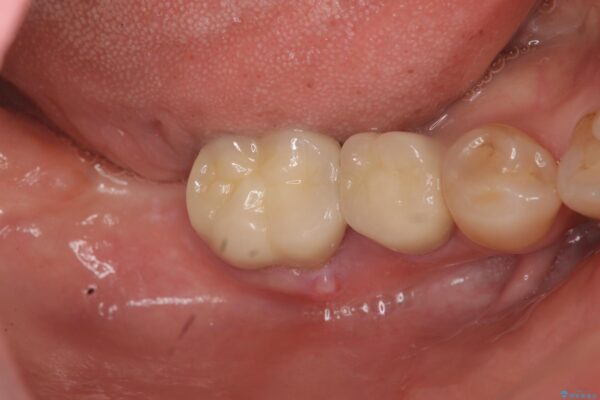

治療後

奥歯から膿のにおいがする インプラントによる機能回復 治療後画像 奥歯から膿のにおいがする インプラントによる機能回復 治療後画像 奥歯から膿のにおいがする インプラントによる機能回復 治療後画像 奥歯から膿のにおいがする インプラントによる機能回復 治療後画像

破折した歯はほとんどの場合抜歯が必要になることが多く、インプラントを用いた咬合機能の回復は、また噛めるようになるだけでなく残っているその他の歯を守る意味でも非常に大きな意味を持ちます。